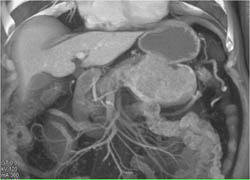

Diagnosis

Islet Cell Tumor